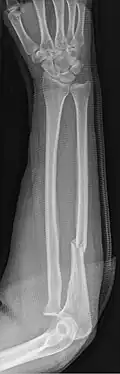

An ulna fracture is a break in the ulna bone, one of the two bones in the forearm.[2] It is often associated with a fracture of the other forearm bone, the radius.[1][3]

An ulna fracture can be a single break as in a so called nightstick fracture, which can be caused by someone being hit on the inside of the forearm often by a stick, notably when they are holding their arm up to protect their head from injury.[2][4] The ulna bone can also break after falling on the forearm or falling on an outstretched arm.[2]

Fractures of the ulna can occur at different levels of the bone: near the wrist, in the middle or near the elbow.[2] The fracture may be confined to the ulna or accompanied with damage to the radius or the wrist or elbow joints.[2]

- Nightstick fracture is a fracture of the middle portion of the ulna without other fractures.[1]

- Monteggia fracture - a fracture of the near to elbow end of the ulna with the dislocation of the head of the radius at the elbow joint.[2]